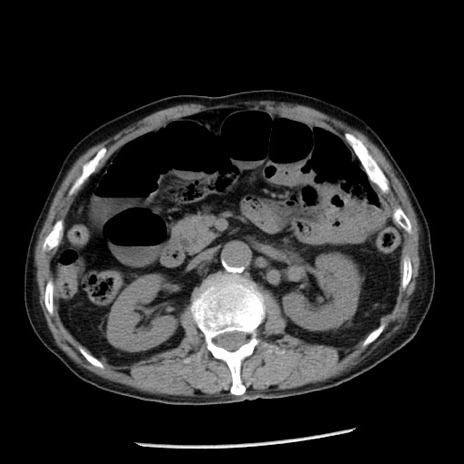

症例26(横断像)

【症例】80歳代男性

【主訴】嘔吐

【現病歴】昨晩2回嘔吐あり、今朝になっても嘔吐あり。来院。

【既往歴】胃潰瘍

【身体所見】意識清明、BT 37.6℃、BP 166/95mmHg、HR 100bpm、SpO2 97%、腹部:平坦・軟、腸蠕動音聴取良好、圧痛なし。

【データ】WBC 21900、CRP 1.46